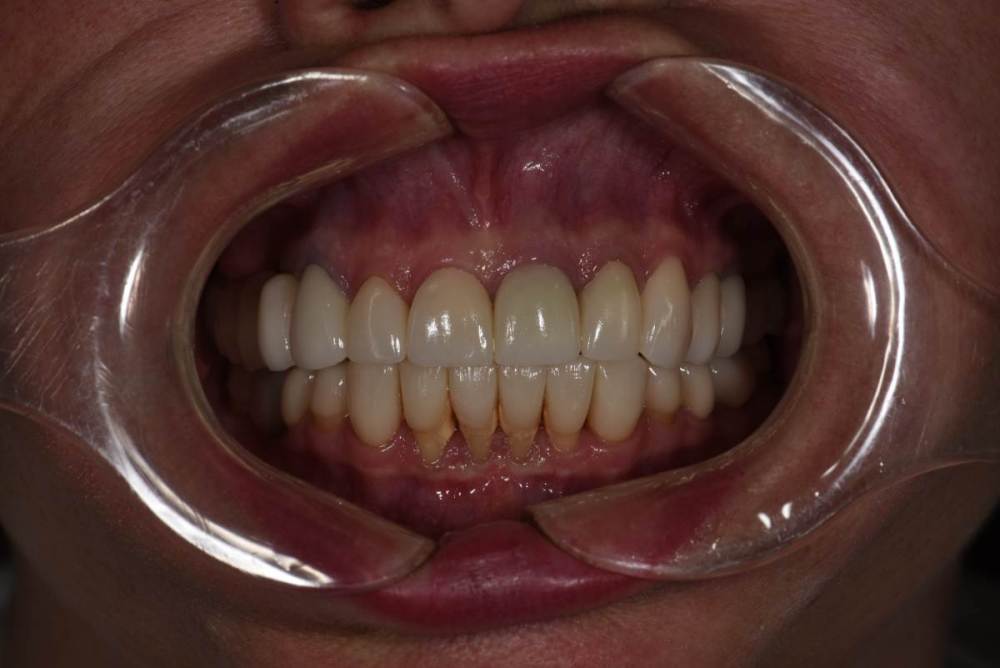

Финал работы:

DSC_3144.thumb.JPG.c9e60b8847f66dc01ba0e6e1113ab39b.JPGDSC_3145.thumb.JPG.1723748a079bc482f1a7e4534aff8f33.JPGDSC_3146.thumb.JPG.6dd4d0eb29dc3e6e92773c3c7892f692.JPGDSC_3147.thumb.JPG.e4f9cc2d841e3b7ff3aa73491ba9b4a3.JPGDSC_3148.thumb.JPG.0f174600adf2a49d65266a0ff665abfd.JPGDSC_3149.thumb.JPG.c9849be795d45b2573488d4545f3843f.JPGDSC_3150.thumb.JPG.6380366ecde7802fa32c6471b8b33883.JPGDSC_3153.thumb.JPG.1420d109d08ed1d6bd63447fe73eeed6.JPGDSC_3154.thumb.JPG.04b902149b3c0f9f2f1bcfa2e310c855.JPG

Фото спустя месяц после фиксации. Сначала нижняя челюсть, потом верхняя. Решение с передними нижними зубами - компромиссное. Все они витальные, имели 2-3 степень подвижности. После исправления положения нижней челюсти и установления правильных окклюзионных контактов - 1-2 степень подвижности. По поводу гигиены пытаемся.